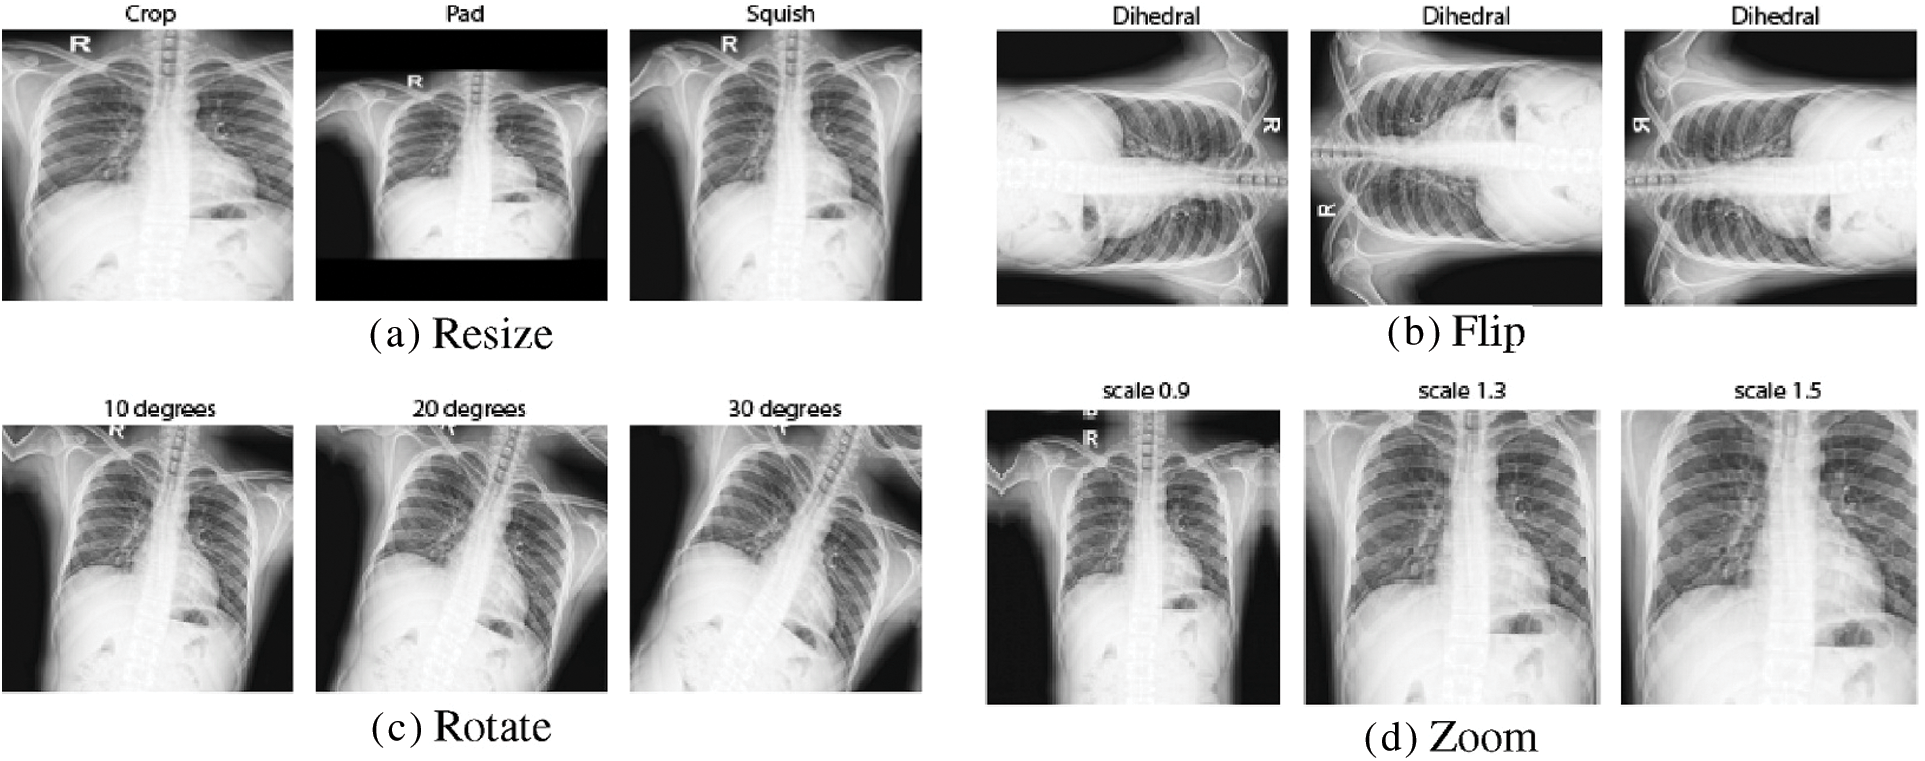

To train deep learning models, an extensive database is needed, and this is a problem with the medical image datasets. To cope with this problem, data augmentation is employed to expand the size of the X-ray image datasets used during training. There are several benefits to data augmentation, including solving overfitting issues and increasing the DCNN model’s scalability. Rotating each detected patch with angles (0°, 90°, 180°, and 270°), then flipping these four images from left to right to obtain eight images for each patch, as illustrated in Fig. 4, was used in this study.

Figure 4: Visualizing the effects of data augmentation on CXR images